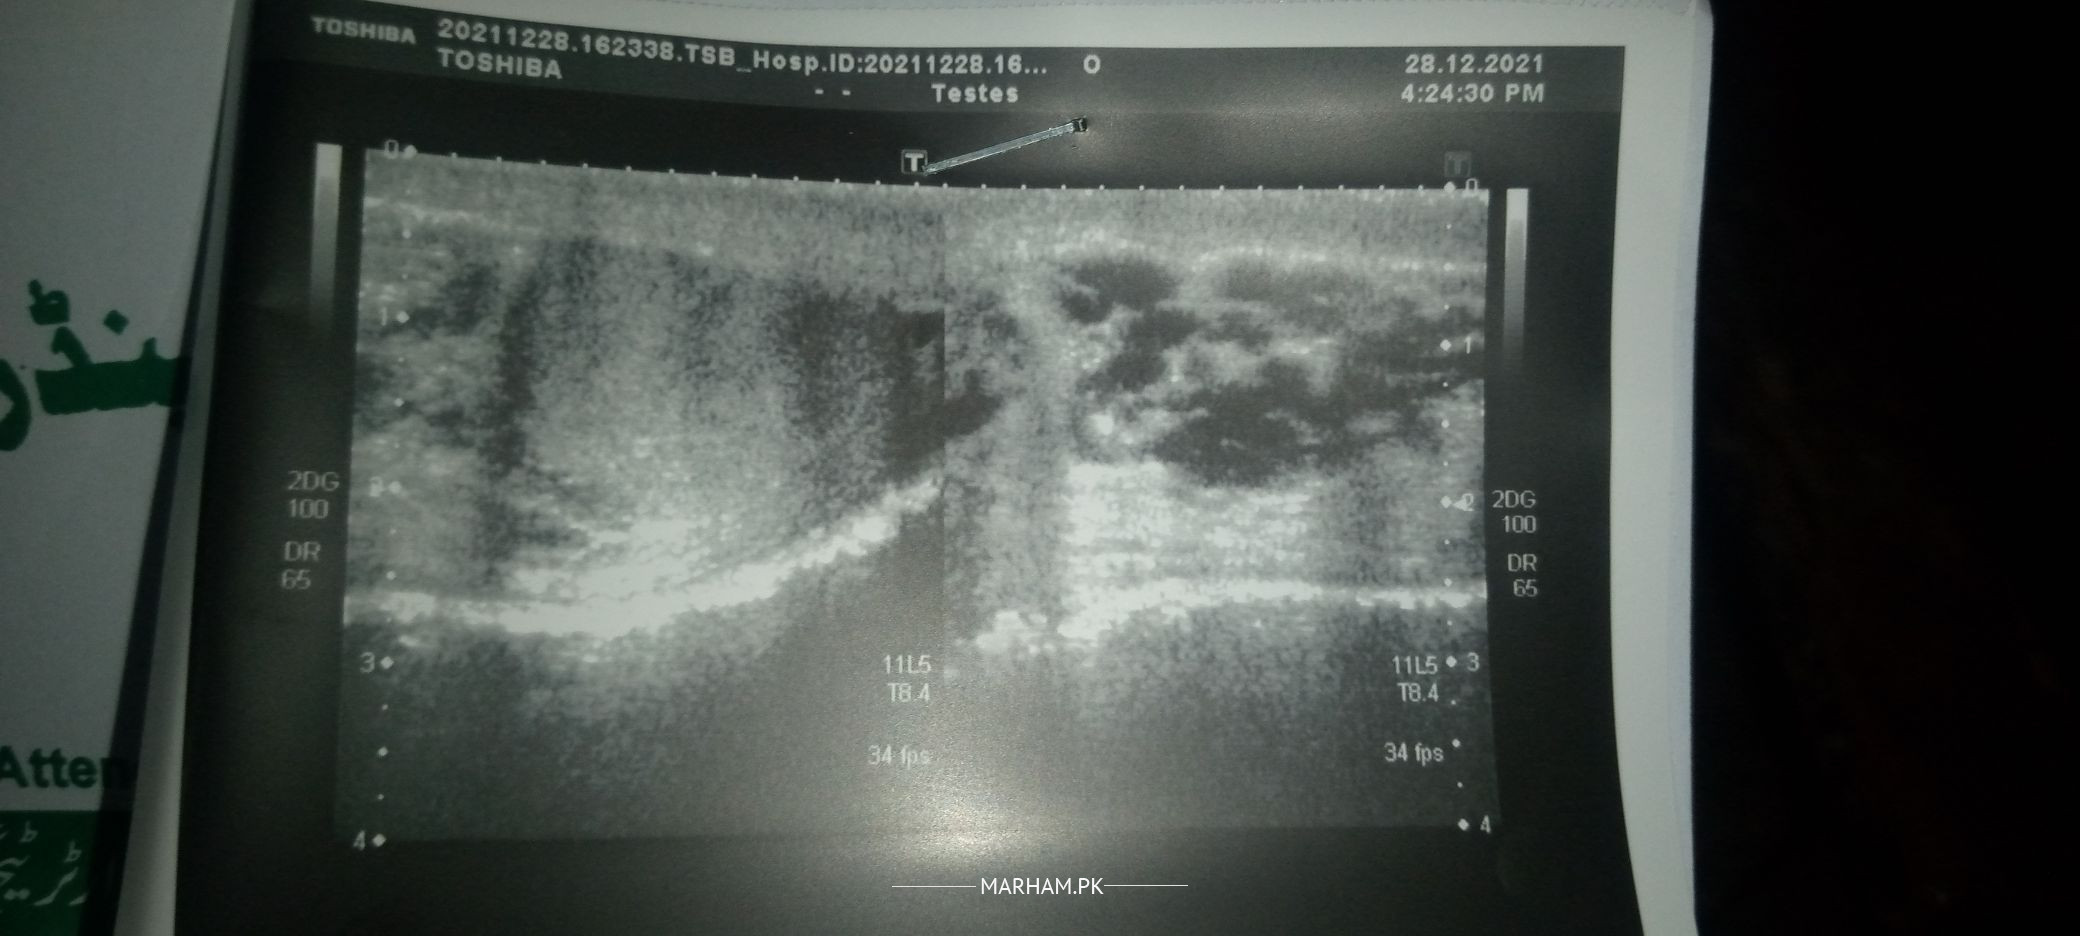

Salam Doctors! I have abnormal testes size i.e right testes is very small as compared to the left one.I noted this probelm a few months there was pain in right told me that without surgery it cannot be I am afraid and try to avoid surgery and want to treate it through Doctors help me which option will be best for me. jazakallah .

varicocele requires surgery